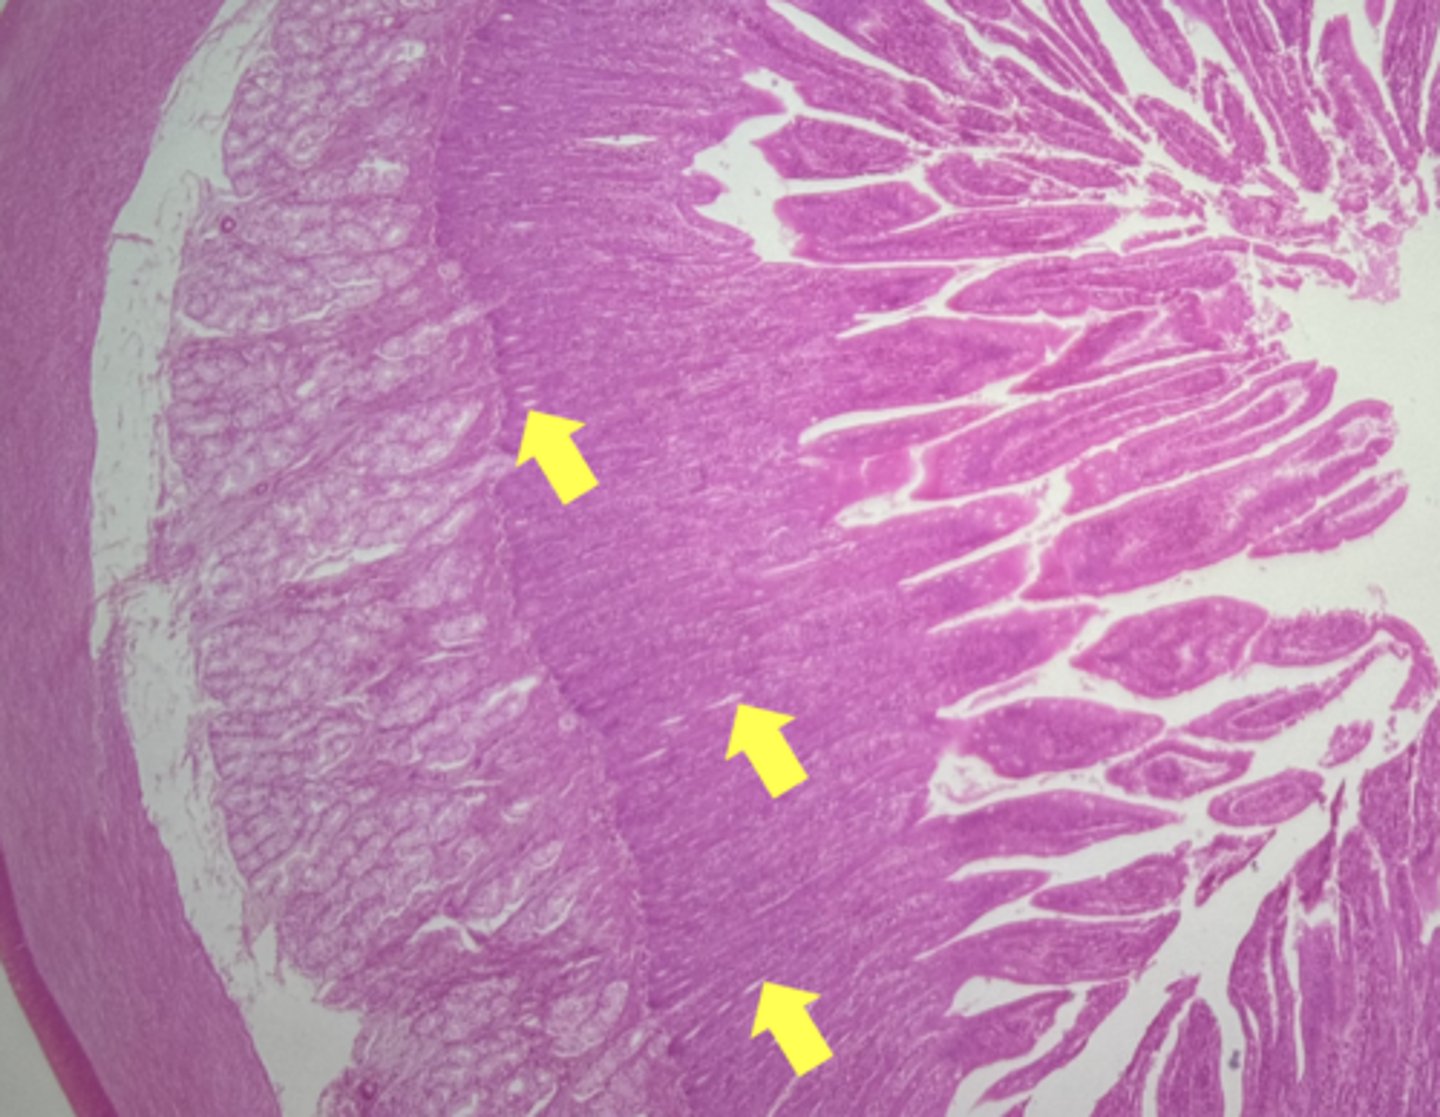

ileum-small intestine

type of tissue

Mucosa

(ilium)

submucosa

muscularis externa

payers patch (KEY CHARACTERISTIC)

circular layer

(ileum)

longitudinal layer

villi

simple columnar epithelium

type of cell

goblet cell- mucous (KEY CHARACTERISTIC)

(ileum-increased # seen here)

type of cell & what it secretes

intestinal crypts

lamina propria

muscularis mucosae